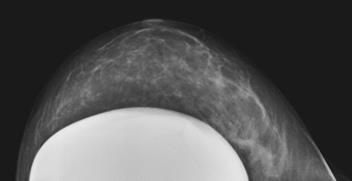

Prótesis

Sombra “simétrica y de densidad “uniforme” de las mamas

Prótesis de ambas mamas densamente calcificadas